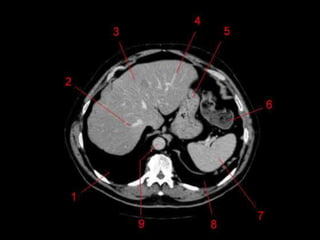

Superfícies e Recessos •Superfície diafragmática e visceral. • Recesso subfrênico – Dividido pelo ligamento falciforme. – Abcessos. • Espaço sub-hepático – Recesso Hepatorrenal • Ligamento coronário, redondo e venoso. • Fossa para vesícula biliar e sulco da veia cava inf. • Porta Hepática

Lobos Anatômicos • LoboDireito e Esquerdo – Dividido pelo ligamento falciforme. • Lobo Quadrado e Lobo Caudado – Fissuras sagitais esquerdas e direitas e divididos pela porta hepática. – Lobo Caudado é superior ao lobo quadrado.

Subdivisão Funcional • Alemde anatômico, os lobos direito e esquerdos são divididos funcionalmente. – Cada um recebe sua tronco primário da artéria hepática, tem sua própria veia portal e drena para o seu próprio ducto hepático. • Caudado também funciona separadamente. – “Terceiro fígado” • Depois pode ser divido em 4 partes e 8 segmentos ressecáveis cirurgicamente.

Subdivisão Funcional • Osoito segmentos são divididos: – A primeira divisão é realizada dividindo através da Porta Hepática, em esquerdo (I a IV) e direito (V a VIII) – A divisão é feita baseada em um relógio – Caudado é o segmento I – No ‘lobo’ esquerdo, o IV separa-se do II e do III pela veia hepática esquerda, representado anatomicamente pelo ligamento falciforme. – II e III se dividem através de uma linha imaginária transversal na altura da porta hepática. – No ‘lobo’ direito, se divide os segmentos através de uma linha transversal e pela veia hepática direita.

Subdivisão Funcional • Fundamentalimportância para Ressecção. • Maioria das lesões são do fígado direito.

Vasos Hepáticos • Veiaporta – Formada pela união da Veia Esplênica e Mesentérica Superior • Artéria Hepática – Segmento da Tronco Celíaco – Dividida em Comum e Própria pelo surgimento da artéria gastroduodenal. • Na maioria das pessoas, a artéria é anterior a veia (91%). Na maioria das pessoas, a artéria hepática direita passa atrás do ducto hepático comum. (64%)

Técnicas de Imagem •US: Primeiro exame pedido ao: 1) dor no hipocondrio direito; 2) testes de função hepáticas anormais; 3) suspeita de malignidade. • TC: Tres fases – Arterial (10 a 20 segundos) – Fase venosa portal ( 30 segundos ) – Fase venosa hepática (60 segundos) • TC Portografia: Metastases.